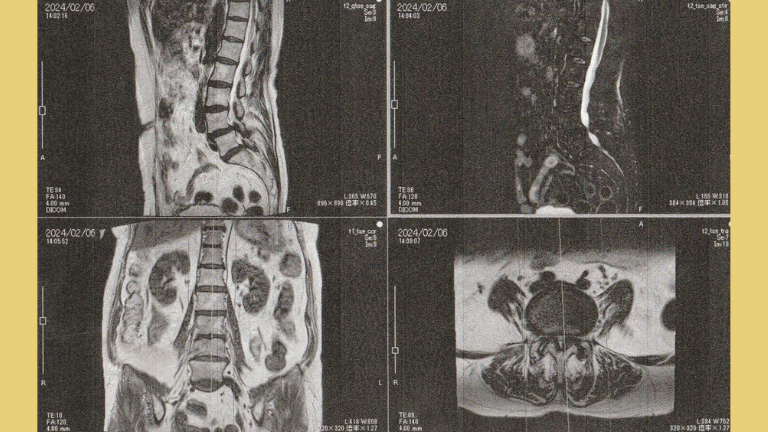

血流状態の把握と神経圧迫による浮腫みが出ている箇所を特定する検査機器であなたの神経痛を見つけ出します。また、診断歴のある患者さんにはMRI検査データをもっていただいております。MRIデータを参考にすることで、どんな状態かを把握し介入できるため、より安全に整体を提供できます。患者さんから「MRIも見てくれるのは安心できる」といっていただけます。